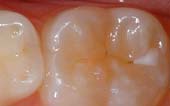

Seal Out Decay

A sealant is a clear or shaded plastic material that is applied to the chewing surfaces (grooves) of the back teeth (premolars and molars), where four out of five cavities in children are found. This sealant acts as a barrier to food, plaque and acid, thus protecting the decay-prone areas of the teeth.